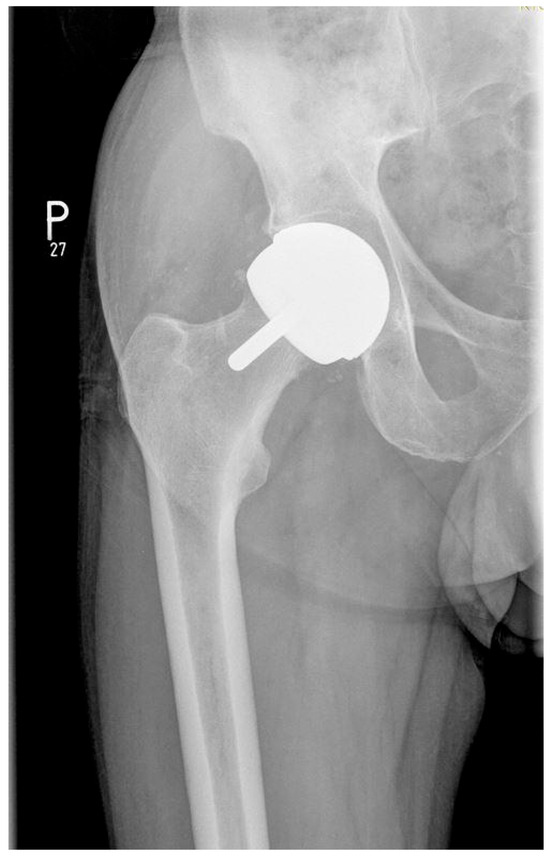

2.1. Description of the Studied Groups and Implants Used